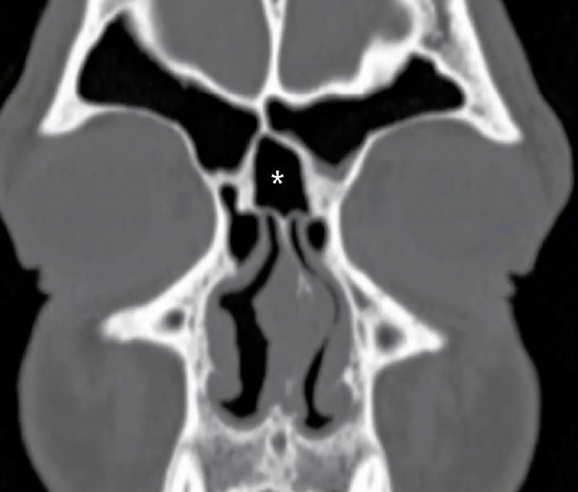

É um fundo cego (asterisco na imagem) formado pela inserção do PU na lâmina papirácea (situação mais prevalente). A drenagem do frontal se dá no meato médio.